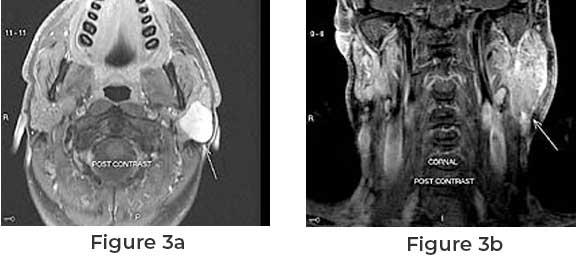

Before surgery, a thorough diagnosis is essential. This often involves imaging tests such as ultrasound, CT scans, or MRIs, as well as a biopsy, where a sample of the tumor is removed and tested for cancerous cells. Symptoms like swelling near the jaw or changes in facial movement may signal the presence of a parotid tumor. However, many benign tumors do not cause pain or noticeable changes.